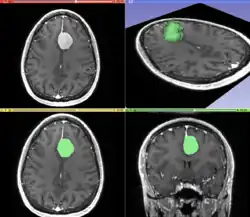

Image and sound processing

Information can take the form of images, sound, video or other multimedia. Bits of information can be streamed via signals. Its processing is the central notion of informatics, the European view on computing, which studies information processing algorithms independently of the type of information carrier – whether it is electrical, mechanical or biological. This field plays important role in information theory, telecommunications, information engineering and has applications in medical image computing and speech synthesis, among others. What is the lower bound on the complexity of fast Fourier transform algorithms? is one of the unsolved problems in theoretical computer science.

|

| FFT algorithms | Image processing | Speech recognition | Data compression | Medical image computing | Speech synthesis |